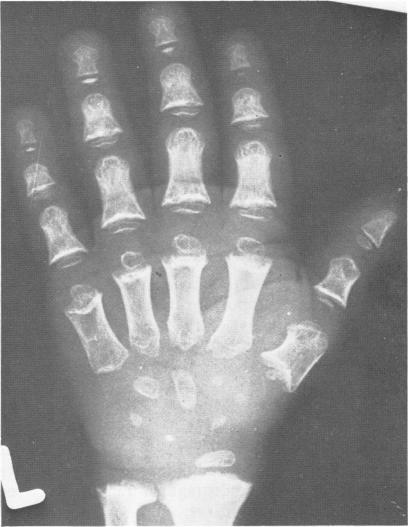

This survey reviews the diagnosis (predominantly radiological) of 32 cases of pseudoachondroplasia from 26 kindreds and illustrates the natural history and varying appearance of the disordered bone growth from infancy to adult life. In addition, an attempt has been made to detect phenotypic differences between autosomal dominant and recessive types (excluding isolated cases), analysing 10 kindreds of dominant inheritance (three in the current survey, seven from published reports) and six of recessive inheritance (three in the current survey, three from published reports). There appears to be no clinical or radiographical feature which clearly distinguishes them, but, using height as a criterion of severity, among those with autosomal recessive inheritance there was a disproportionate number of the most severely affected cases and there also appears to be very little intrafamilial variation. It is possible that pseudoachondroplasia can be subdivided into autosomal dominant mild and severe and autosomal recessive mild and severe, but full delineation must await elucidation of the basic defect at biochemical and molecular levels.

本调查回顾了来自26个家族的32例假软骨发育不全病例的诊断(主要是放射学诊断),并阐述了该疾病从婴儿期到成年期骨骼生长紊乱的自然病史及不同表现。此外,还尝试检测常染色体显性和隐性类型(不包括散发病例)之间的表型差异,分析了10个显性遗传家族(本次调查中有3个,已发表报告中有7个)和6个隐性遗传家族(本次调查中有3个,已发表报告中有3个)。似乎没有能明确区分它们的临床或影像学特征,但是,以身高作为严重程度的标准,在常染色体隐性遗传患者中,受影响最严重的病例比例过高,而且家族内差异似乎也很小。假软骨发育不全有可能可细分为常染色体显性轻度和重度以及常染色体隐性轻度和重度,但要进行全面分类,必须等待在生化和分子水平上阐明其基本缺陷。